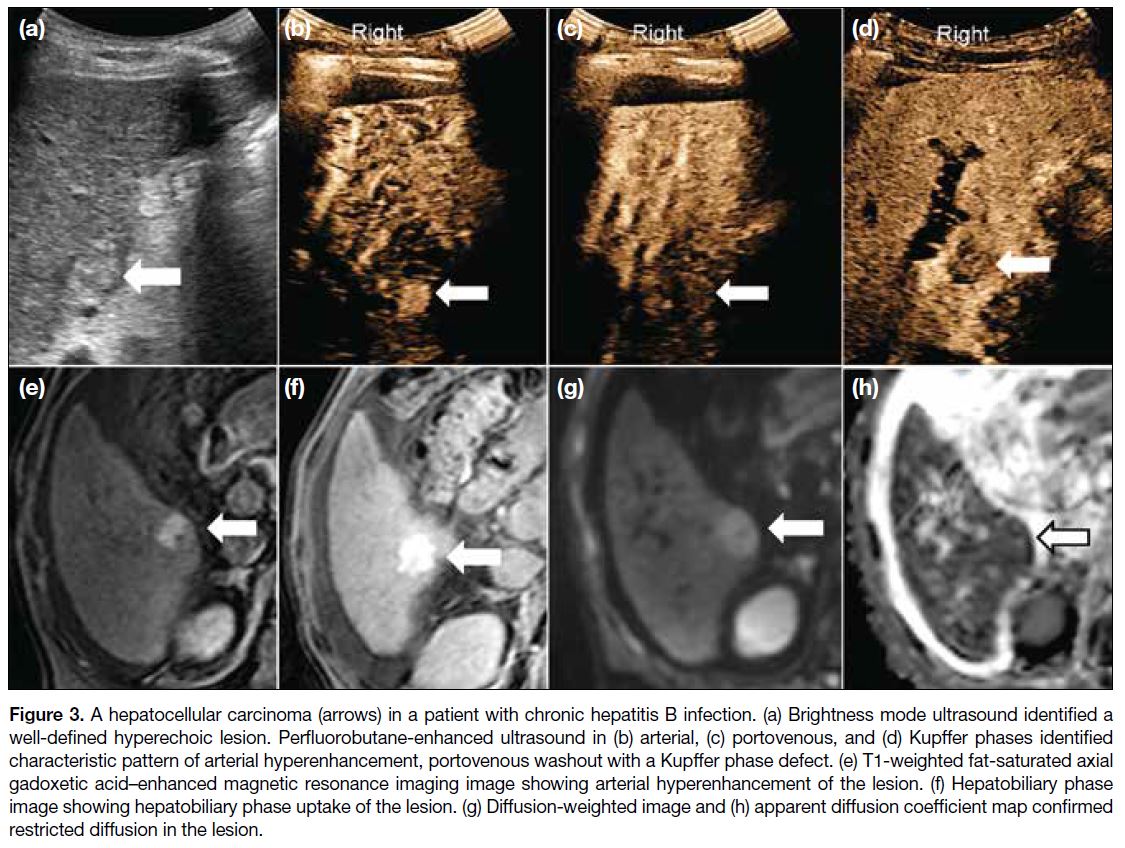

B-mode ultrasound and 6% (n = 3) by PFB-CEUS. A total of four small HCCs were identified in our cohort (Table 7). Figures 2, 3, 4, and 5 show the key imaging features of these four HCCs found in our cohort.

Figure 3. A hepatocellular carcinoma (arrows) in a patient with chronic hepatitis B infection. (a) Brightness mode ultrasound identified a

well-defined hyperechoic lesion. Perfluorobutane-enhanced ultrasound in (b) arterial, (c) portovenous, and (d) Kupffer phases identified

characteristic pattern of arterial hyperenhancement, portovenous washout with a Kupffer phase defect. (e) T1-weighted fat-saturated axial

gadoxetic acid–enhanced magnetic resonance imaging image showing arterial hyperenhancement of the lesion. (f) Hepatobiliary phase

image showing hepatobiliary phase uptake of the lesion. (g) Diffusion-weighted image and (h) apparent diffusion coefficient map confirmed

restricted diffusion in the lesion.

in the parenchyma, 9 cm from the skin surface (Figure 3). The difficulty of evaluating deep lesions by PFB-CEUS